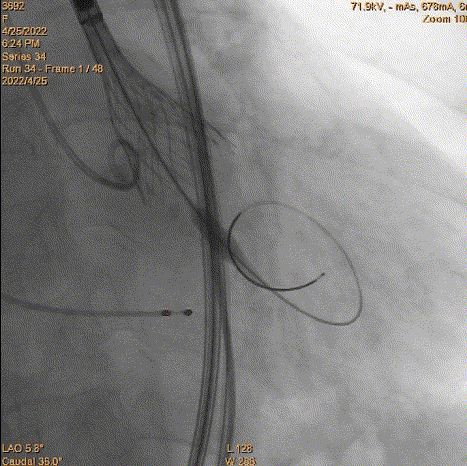

4、跨瓣:瓣膜跨瓣出现困难,计划使用圈套器。由于没有22F大鞘,内连鞘无法拆卸,选择左侧穿刺导入导管。右侧双导丝,送入Lunderquist,心室较大。扩张后,血压较稳定。经尝试无法退球囊,撤出系统。通过对侧使用抓捕器,将导丝全撤,导入AL1.0导管重新跨瓣。鉴于左侧入路有角度,使用泥鳅导丝带上导管,做圈套器。顺利抓住J型导丝,抓捕器顺利抓捕瓣膜过瓣。

重新过瓣

瓣膜过瓣